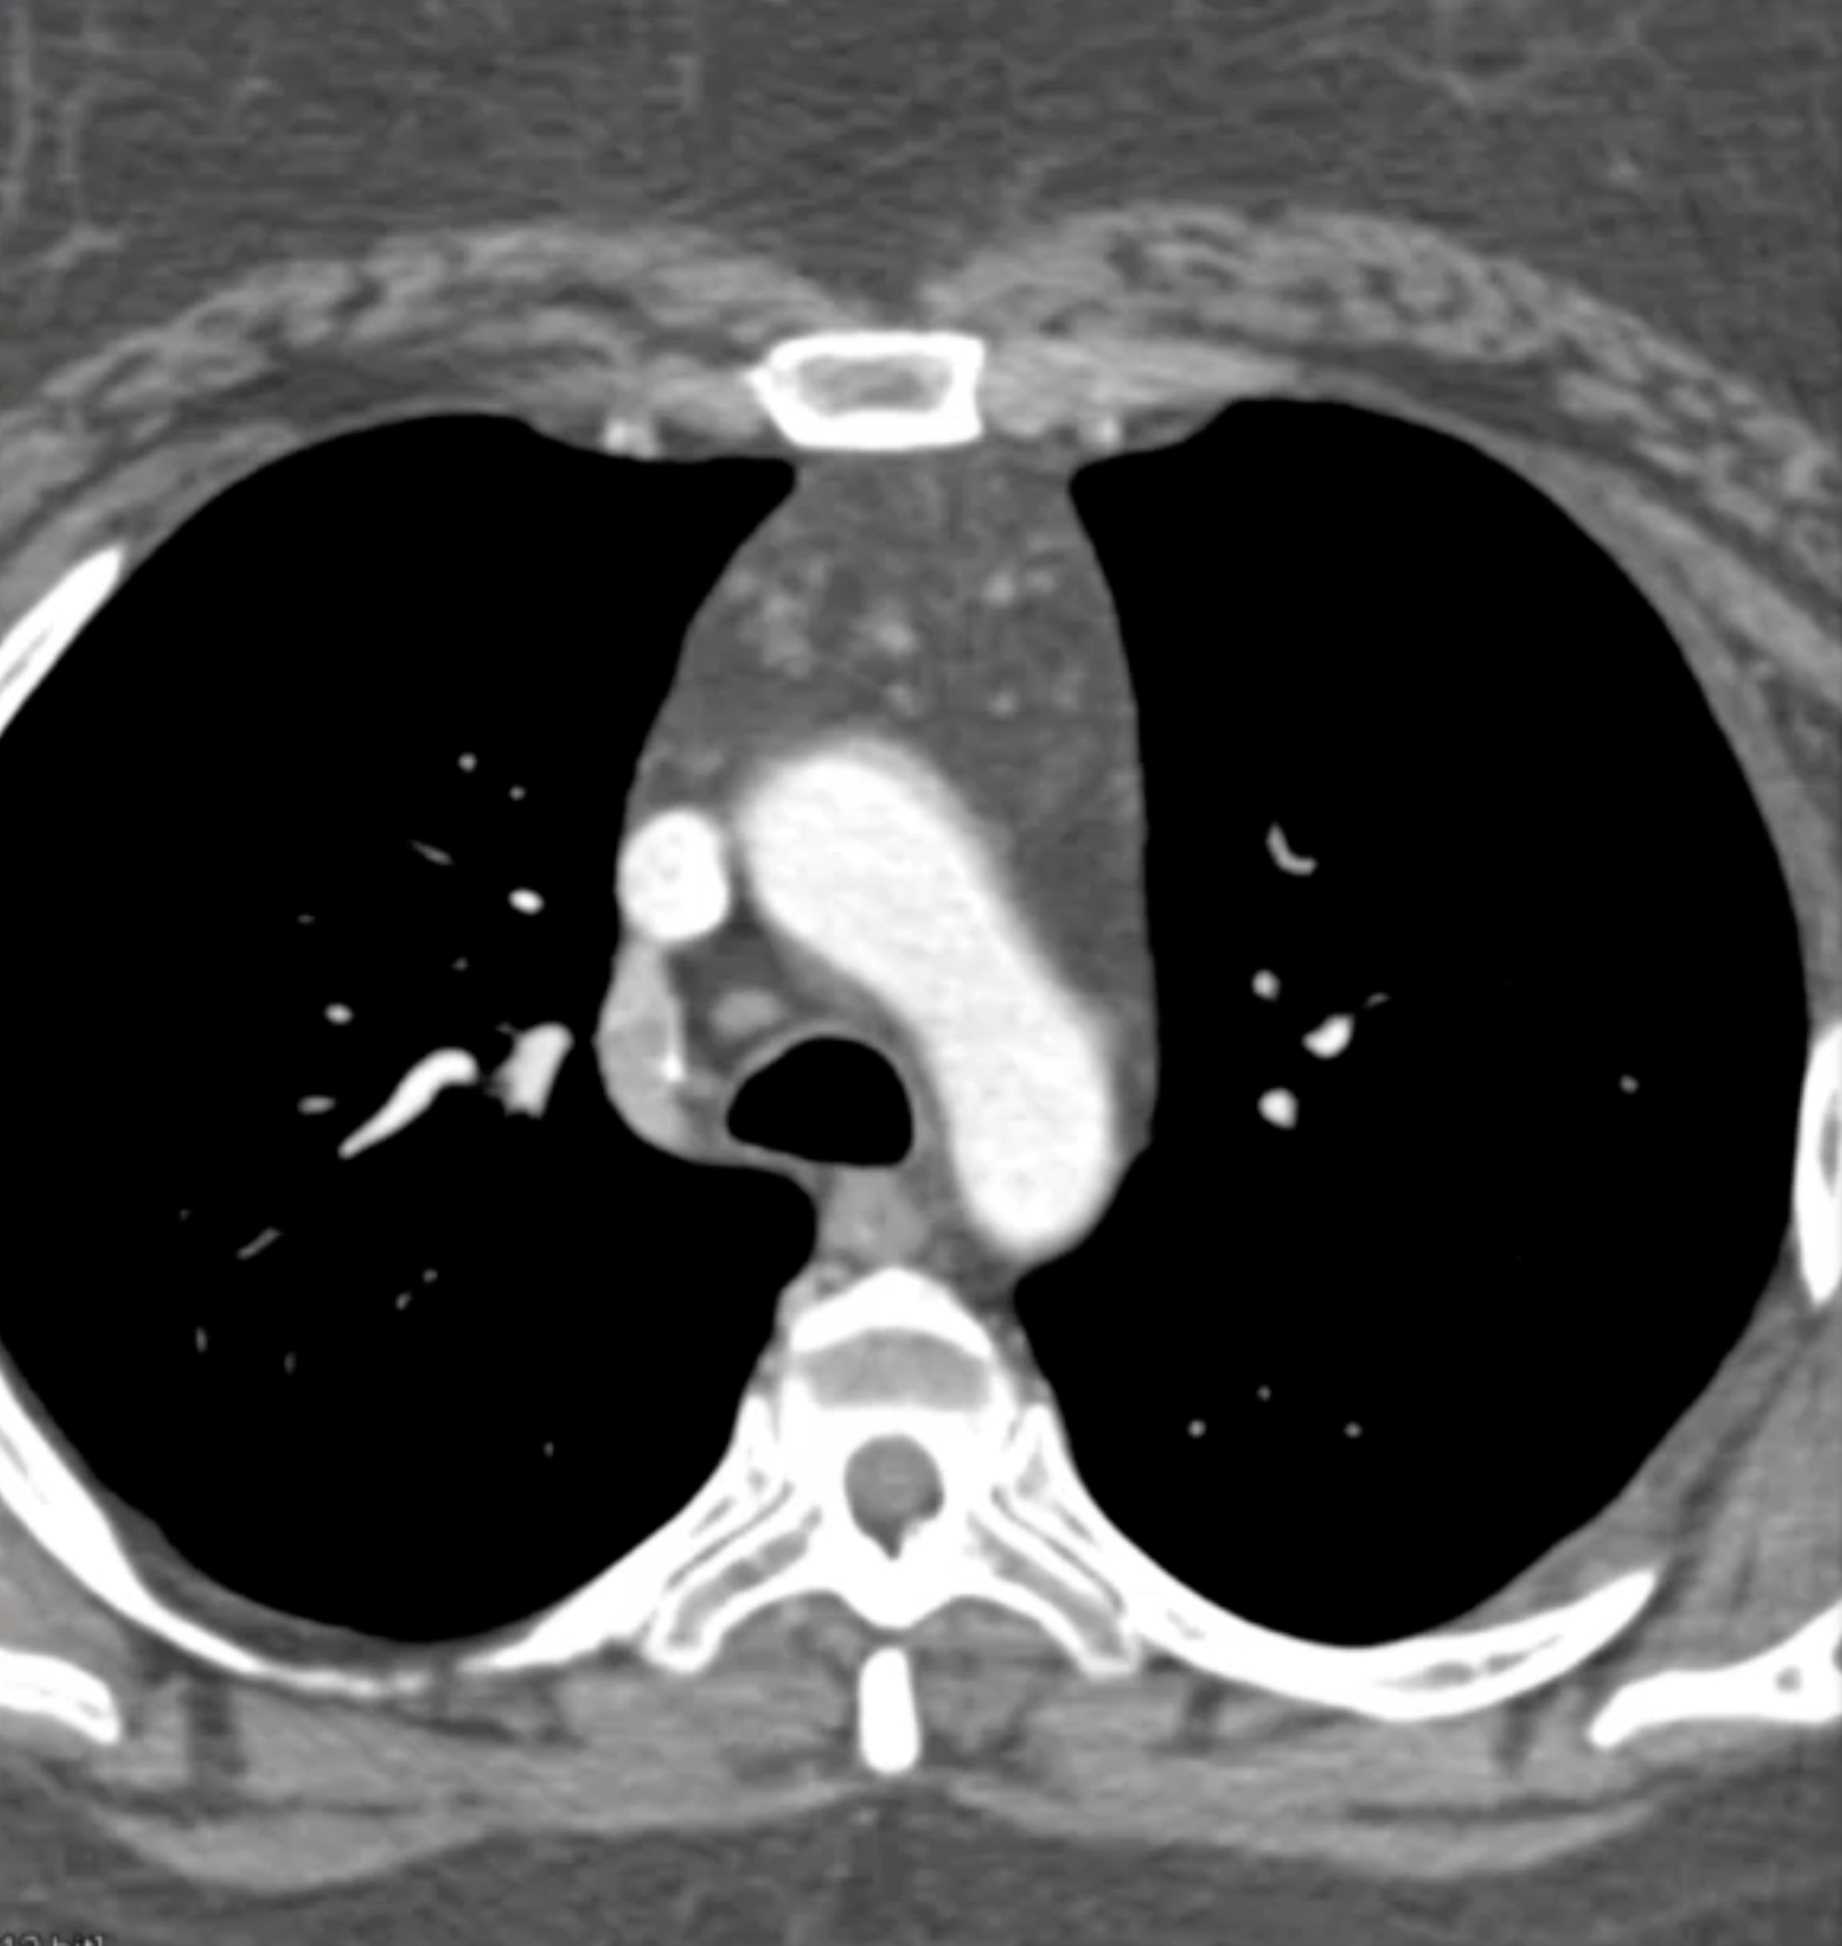

Primary Spindle Cell Carcinoma of the Right Ventricle